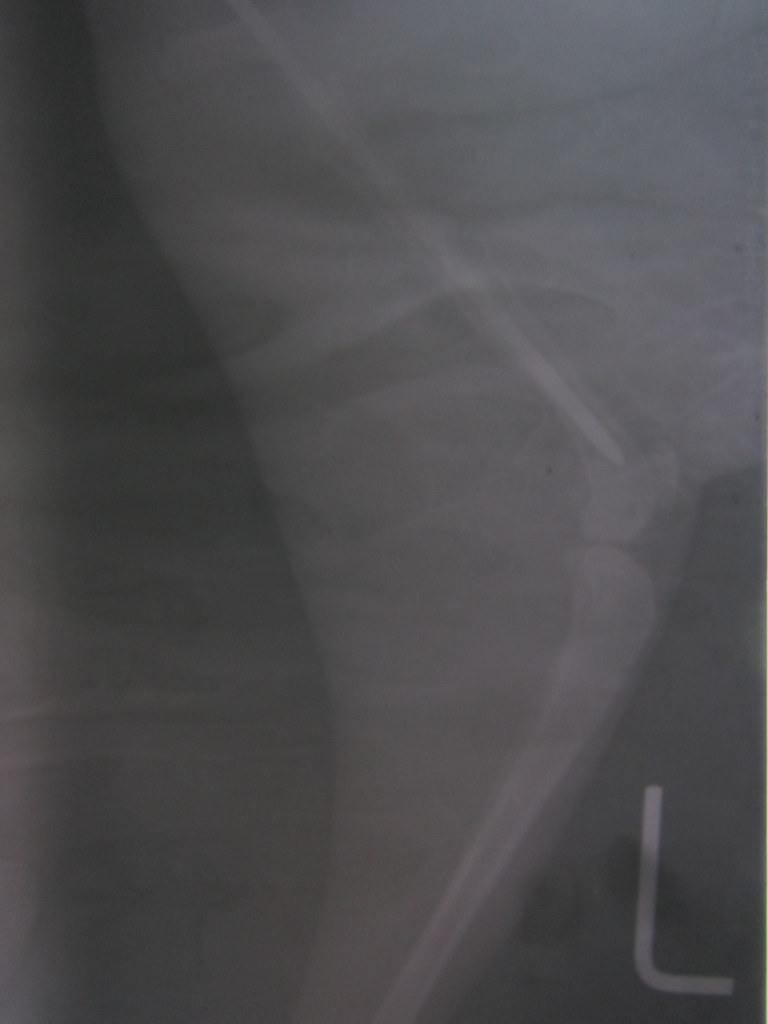

From www.reddit.com

Cat, femoral head fracture... r/Radiology Cat Femur Fracture Repair The 2.4 mm plating system is a highly appropriate implant for cat femoral fractures, and 4.0 mm interlocking nails have also been shown to be appropriate in most cats. These fractures are usually the result of. Fractures of the femur (thigh bone) are some of the most common fractures seen in cats. Complications of femoral fracture repair. The femur is. Cat Femur Fracture Repair.